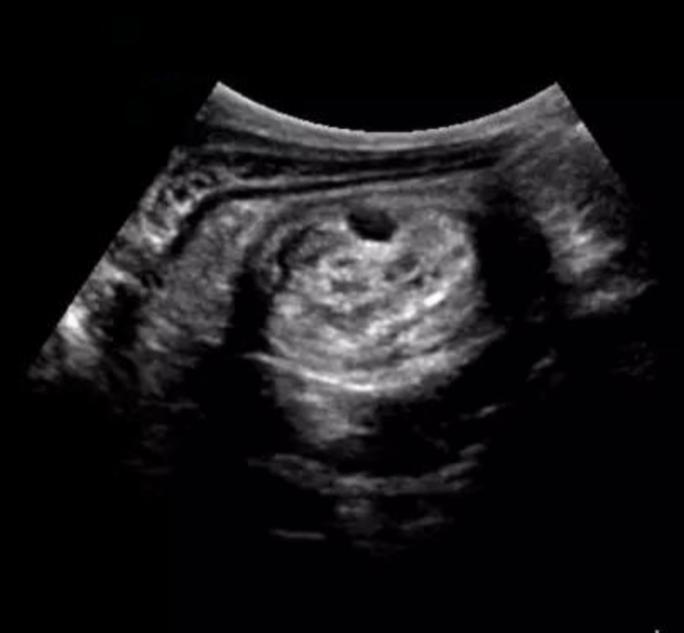

- 做腹部B超检查,腹部有典型的同心圆回声。